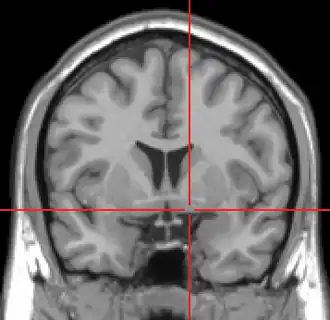

MRI showing a coronal plane of the head with marks showing the location of the substantia innominata, the region in which the nucleus basalis is found. | |

The nucleus basalis in humans is a somewhat diffuse collection of large cholinergic neurons in the basal forebrain.[2] The main body of the nucleus basalis lies inferior to the anterior commissure and the globus pallidus, and lateral to the anterior hypothalamus in an area known as the substantia innominata.[1] Rostrally, the nucleus basalis is continuous with the cholinergic neurons of the nucleus of the diagonal band of Broca.[1] The nucleus basalis is thought to consist of several subdivisions based on the location of the cells and their projections to other brain regions.[2] Occasional neurons belonging to the nucleus basalis can be found in nearby locations such as the internal laminae of the globus pallidus and the genu of the internal capsule.[1]